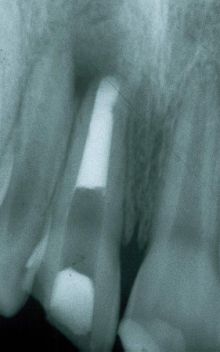

En este paciente, el incisivo superior presentaba una fractura traumática y fue tratado endodónticamente. Nótese el gran espacio radicular debido al diente inmaduro, ápice abierto.

El diente fue tratado endodónticamente con apexificación utilizando hidróxido de calcio y luego se rellenó con gutapercha. Observe el gran espacio del canal y la delgada estructura interior del diente.

El diente fue restaurado como se ha descrito anteriormente, se grabó el canal radicular, se colocó adhesivo y un composite híbrido dual. Para este caso se utilizaron dos piezas de Ribbond de 3 mm. que se colocaron en la resina empleando un instrumento para endodoncia de Ribbond.

Debido a que el paciente era un joven adolescente la restauración final fue una Clase IV de composite. En la radiografía se ve como la fibra Ribbond se ha unido al composite.

Vista postoperatoria tras 3 años y medio

Combinación de composite microrelleno e híbrido.

Restauración de clase IV.